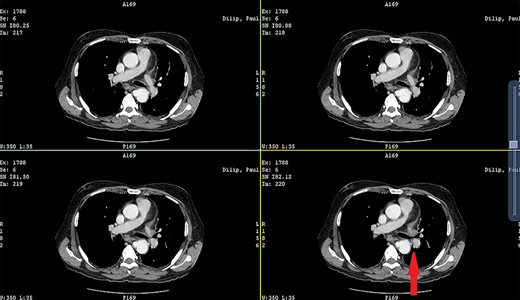

Patient 1: a 52-year-old woman, non-diabetic, non-hypertensive, was referred to the emergency with a history of large-volume, frank hematemesis (four episodes in 3 days). Positive history included recurrent cough for the past 1 year and low-grade fever for 3 months. No history of dysphagia, jaundice, abdominal distension, pain abdomen or altered sensorium. No history of chronic medications (oral anticoagulants or anti-platelets), analgesic intake or any substance abuse. She had received four units of packed red cells at an outside facility prior to admission. She was conscious, oriented, hemodynamically labile (heart rate: 110/min; BP: 86/60 mm Hg) with mild fever (99°F). General survey revealed obvious pallor. All other system examinations were within acceptable limits. Her hemoglobin (Hb) was 7.3 gram%, total leukocyte count (TLC) was 6400 cells/mm3, total bilirubin was 1.31 mg/dl and total protein was 4.75 gram%. An urgent UGI endoscopy revealed an opening in the posterior wall of the lower third of the esophagus, with a diverticulum. Inflammatory changes were noted in the diverticulum (Fig. 1). Contrast-enhanced computed tomogram (CECT) revealed erosion of the pouch into the thoracic aorta (Fig. 2), and a diagnosis of AEF with acute UGI hemorrhage was made.

Patient 2: a 48-year-old hypertensive, non-diabetic gentleman, presented to the emergency with one episode of massive hematemesis. There was no history of dysphagia, jaundice, abdominal distension, pain abdomen or altered sensorium. Past history was significant for percutaneous coronary intervention with two drug-eluting stents performed 3 years ago, for which he was on aspirin. He had normal mentation, his BP was 90/60 mm Hg and his heart rate was 120/min. A general survey revealed pallor and rest of the systemic examination was normal. His Hb was 6.1 gram% and TLC was 6300 cells/mm3. Liver function tests, coagulation parameters, renal function and electrolytes were normal. Chest X-ray was unremarkable. He was initially resuscitated with intravenous fluid, packed red blood cells and a proton-pump inhibitor infusion. An urgent UGI endoscopy revealed a large depressed ulcer with a red spot located in the middle third of the esophagus. A diverticulum was seen in the lower end of the ulcer (Fig. 7). An endoscopic clip was applied to the margin for ease of identification. CECT thorax revealed a 6 cm saccular thoracic aortic aneurysm distal to the left subclavian artery, eroding into the esophagus (Fig. 8).